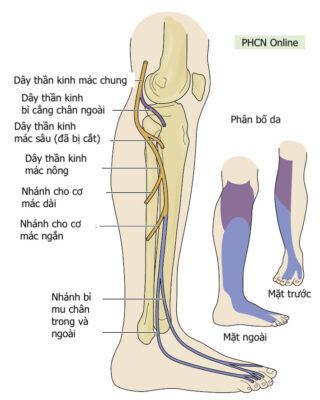

Nhắc lại giải phẫu

Dây thần kinh mác chung là một dây thần kinh lớn chi phối cho chi dưới. Nó là một trong hai nhánh chính của dây thần kinh tọa (nhánh kia là thần kinh chày) và nhận các sợi từ các ngành sau của các rễ thần kinh từ L4 đến S2. Dây thần kinh mác chung tách dây thần kinh chày ở phía dưới mặt sau đùi gần hố khoeo. Sau khi tách khỏi dây thần kinh chày, nó tiếp tục chạy xuống đùi, chạy phía sau dưới đến cơ nhị đầu đùi (phân nhánh vận động cho đầu ngắn của cơ nhị đầu đùi), và bắt chéo ra ngoài đến đầu cơ bụng chân ngoài qua vách gian cơ sau. Sau đó, dây thần kinh này tiếp tục đi ngang ra ngoài, vòng quanh cổ xương mác. Trước khi đến đầu xương mác, nó phân nhánh cảm giác (bì cẳng chân ngoài) để phân bố cảm giác cho da mặt trên ngoài cẳng chân. Gần đầu xương mác, dây thần kinh mác chung chia thành hai nhánh tận, dây thần kinh mác nông (superficial peroneal nerve, SPN) và dây thần kinh mác sâu (deep peroneal nerve , DPN).

Dây thần kinh mác nông chi phối khoang ngoài của cẳng chân, còn dây thần kinh mác sâu chi phối khoang trước của cẳng chân và mu bàn chân.

- Dây thần kinh mác nông chủ yếu là dây thần kinh cảm giác, phân bố cho:

- Về vận động: Khoang ngoài

- Cơ mác dài

- Cơ mác ngắn

- Về cảm giác:

- Trước ngoài cẳng chân, hầu hết mu bàn chân

- Về vận động: Khoang ngoài

- Dây thần kinh mác sâu chủ yếu là vận động, phân bố cho:

- Về vận động: Khoang trước

- Cơ chày trước

- Cơ duỗi ngón cái dài

- Cơ duỗi các ngón dài

- Cơ mác ba

- Về cảm giác

- Khoảng kẽ ngón thứ nhất mu chân.

- Về vận động: Khoang trước

Hình 1: Phân bố cảm giác và vận động của dây thần kinh mác chung (màu tím) và mác nông (xanh).

Hình 2. Phân bố cảm giác và vận động của Dây thần kinh mác sâu

- Giảm cảm giác ở mặt trên ngoài cẳng chân (Hình 1) gợi ý một tổn thương ở cao hơn đầu xương mác (nghĩa là dây thần kinh mác chung). Đánh giá cơ vặn trong bàn chân, để loại trừ tổn thương đồng thời của dây thần kinh chày (nghĩa là tổn thương ở dây thần kinh tọa), tốt nhất với bàn chân gập mu nhẹ.

- Giảm hoặc rối loạn cảm giác ở phần dưới ngoài cẳng chân và hầu hết mu bàn chân gợi ý ảnh hưởng đến dây thần kinh mác nông hoặc phần này của dây thần kinh tọa (Hình 1).

- Trường hợp ảnh hưởng đến dây thần kinh mác sâu, có giảm cảm giác hoặc dị cảm dọc theo khoảng kẽ thứ nhất của bàn chân (Hình 2).